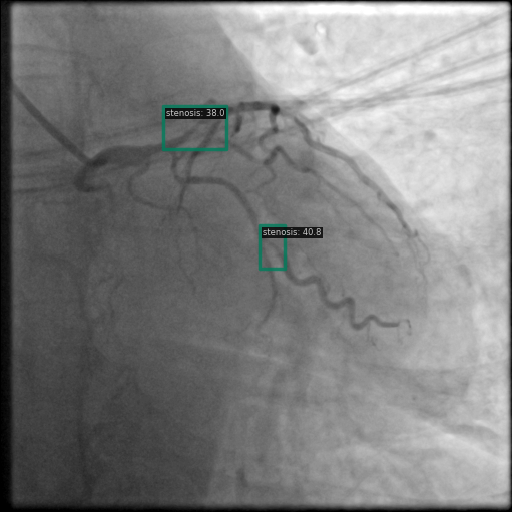

以下图像展示了每个模型在相同冠状动脉造影图像上的表现:

图6 Grounding DINO 的检测显示具有明确标签的高置信度狭窄检测。

3.2 Grounding DINO 检测模式

Grounding DINO 识别出了更多的区域,但有时由于过度检测导致预测混乱。该模型似乎利用其跨模态理解来检测更广泛的狭窄表现。如图 6 和图 9 所示,Grounding DINO 通常以不同置信度分数检测多个狭窄区域。虽然这增加了捕获所有狭窄区域的可能性,但同时也提升了假阳性的可能性。

图9 Grounding DINO 检测显示多个具有置信度分数的检测区域。